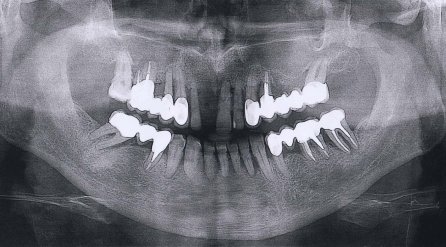

В заключении, отвечая на Ваш вопрос, советую найти хорошую стоматологическую клинику. Необходимо сделать рентгеновские снимки, чтобы понять степень поражения костной ткани.

• Ваше желание иметь несъемную конструкцию понятна. После внимательного изучения панорамного снимка и подтверждения пародонтоза можно с уверенностью констатировать, что несъемного метода решения с опорой на имеющиеся Ваши зубы, к великому сожалению, нет. Вам нужна тотальная базальная имплантация или съемное протезирование.